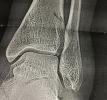

Объектами исследования выступал комплекс документарных материалов, имеющих решающее значение для оценки качества оказанных медицинских услуг. Эти материалы были представлены в бумажном виде и на рентгеновской плёнке, их состояние было признано удовлетворительным для проведения анализа. Комплект включал в себя как оригиналы, так и копии документов, содержащие как рукописные, так и печатные записи.

• Рентгеновские снимки (2 шт.).

В процессе работы экспертов были применены методы тщательного анализа и сопоставления данных, полученных из различных источников. Производилось детальное изучение медицинских карт и рентгеновских снимков, а также всех представленных в деле документов. Были использованы цитирование ключевых фрагментов и сравнительный анализ полученных сведений со стандартами, регламентированными федеральными законами, постановлениями и приказами Министерства здравоохранения Российской Федерации, включая Федеральный закон от 31.05.2001 №73-ФЗ «О государственной судебно-экспертной деятельности в Российской Федерации», Федеральный закон от 21.11.2011 №323-ФЗ «Об основах охраны здоровья граждан в Российской Федерации», Постановление Правительства РФ от 17.08.2007 №522 «Об утверждении Правил определения степени тяжести вреда, причиненного здоровью человека», а также Приказы Минздрава России от 10.05.2017 №203н, устанавливающий критерии оценки качества медицинской помощи, и от 12.11.2012 №901н, регламентирующий порядок оказания медицинской помощи по профилю «травматология и ортопедия». Все эти меры позволили экспертам сформулировать обоснованные ответы на поставленные перед ними вопросы с использованием принципов формальной логики.